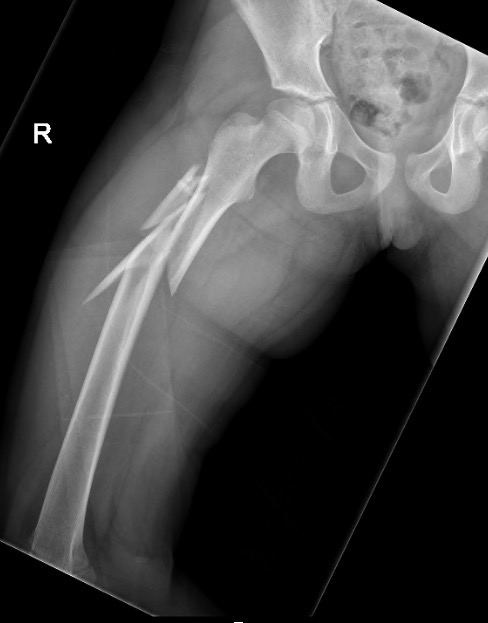

[Ortho] Перелом бедра, девочка 11 лет

Поступила пациентка 11 лет после падения с электросамоката.

Других повреждений нет.

Перелом закрытый. Какой вариант фиксации оптимален, на ваш взгляд?